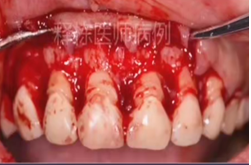

局麻下翻瓣